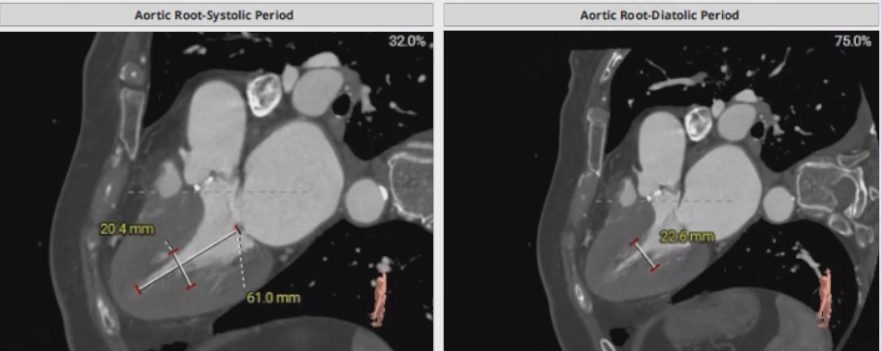

术前CT评估示

Type-1型二叶瓣,瓣叶增厚,中度钙化;L-R交界纤维钙化粘连。收缩期瓣环周长68.8 mm,平均径21.9 mm;LVOT周长65.5 mm,平均径20.9 mm;舒张期瓣环周长69.6 mm,平均径22.1mm;LVOT周长65.3mm,平均径20.8 mm;瓣上2/4/6/8/10 mm,预计可推开空间周长69.2/69.2/65.6/66.1/66.4 mm。

主动脉窦部L30.3 mm,R30.6 mm,N36.7 mm,STJ均径27.0 mm。

升主动脉40 mm,高度处均径35.0 mm,50 mm,高度处均径37.0 mm。

收缩期左心室长径61.0 mm,短径20.4 mm,舒张期左心室短径22.6 mm。

瓣环角度54°,造影体位。

左冠开口高度11.7 mm,右冠开口高度16.3 mm,冠脉风险较低。